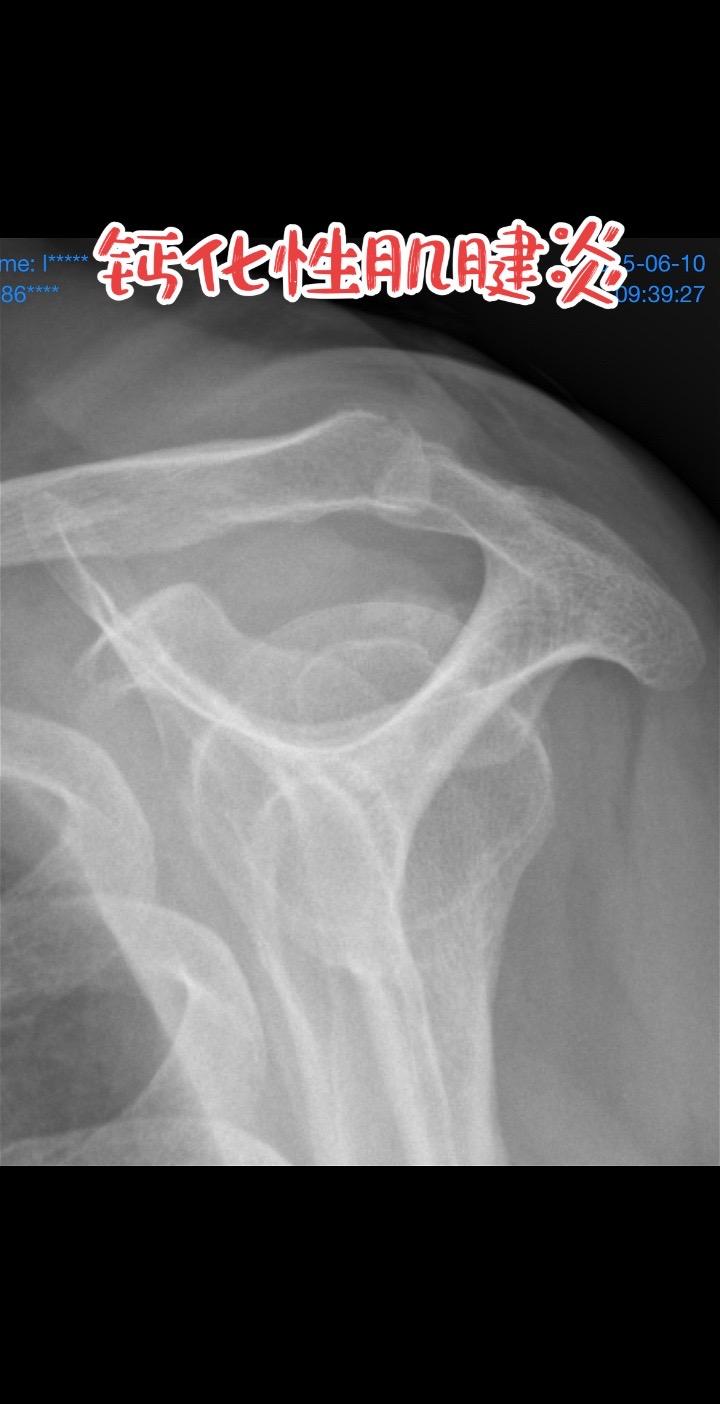

钙化性肌腱炎。半夜痛醒、抬手都困难,片子里亮亮的那一团就是罪魁祸首!